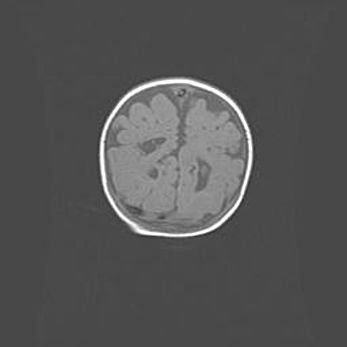

Открытая гидроцефалия.

Возраст: 9 месяцев 12 дней

Вес: 6800 г

Пол: мужской

Окружность головы: 41,5 см

Срок гестации: 28 недель

Гидроцефалия головного мозга у новорожденных имеет характерный признак: опережающий рост окружности головы приводит к визуально хорошо определяемой гидроцефальной форме сильно увеличенного в объёме черепа. Детские неврологи определяют следующие симптомы гидроцефалии у грудничков: выбухающий напряжённый родничок, частое запрокидывание головы, смещение глазных яблок к низу.